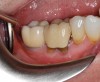

Healing of the site was observed on several occasions post-surgery, including at 4.5 months (Figure 18). Excellent gingival and underlying bone contours were revealed in 24-month photographs and panoramic x-ray (Figure 19 through Figure 21).

Fig 19. Restoration at 24 months, occlusal view (Fig 19) and buccal view (Fig 20).

Figure 19

Fig 20. Restoration at 24 months, occlusal view (Fig 19) and buccal view (Fig 20).

Figure 20